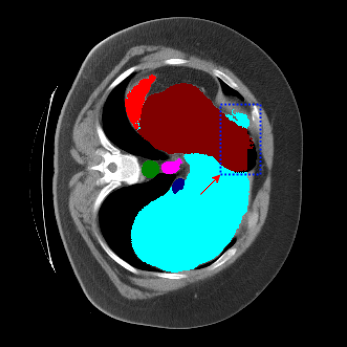

| Ground Truth | LoGoNet | DiNTS Search |

|---|---|---|

![]() |

We begin by qualitatively inspecting our model. Figure 3 compares the output of LoGoNet to the best performing baseline model in BTCV dataset, i.e., DiNTS Search (more qualitative comparisons can be found in appendix section 11). We see that our model particularly excels in segmenting organ boundaries. This can be attributed to our effective strategy for extracting local-range dependencies, which plays a crucial role in extracting details from input data. Our model’s adeptness in capturing long-range dependencies allows it to grasp contextual information that extends over significant distances within the data. Simultaneously, its proficiency in handling short-range dependencies ensures precision in capturing localized patterns.